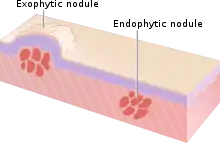

In medicine, nodules are small firm lumps, usually greater than 1 cm in diameter.[1][2] If filled with fluid they are referred to as cysts.[2] Smaller (less than 0.5 cm) raised soft tissue bumps may be termed papules.[3]

Nodules are small firm lumps usually greater than 1 cm in diameter, found in skin and other organs.[1][2] If filled with fluid they are usually softer and referred to as cysts.[2] Smaller (less than 0.5 cm) raised soft tissue bumps may be termed papules.[3]